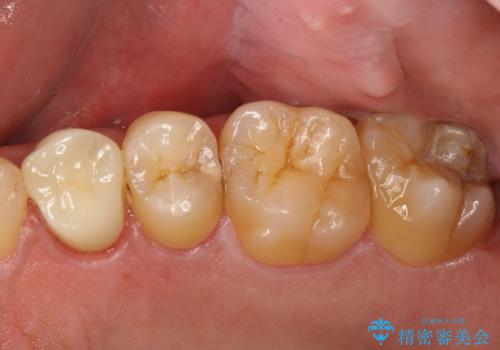

[フルジルコニアクラウン] 老朽化した銀歯を白く